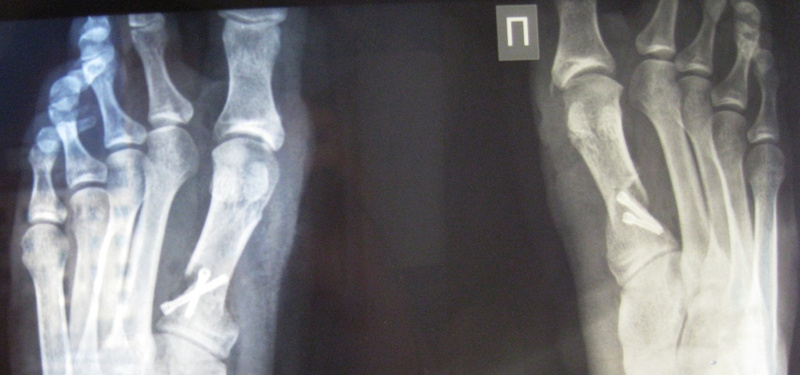

Оперировал Пахомов, хотя записывалась я у другого, они как-то все поменяли в последние дни. У меня в каждой ступне по 2 винта (скрепляют большой палец и кость в стопе) - это была остеотомия. Шрамы на мой взгляд не бросаются в глаза (может завтра сфотаю и выложу до и после). Фитнесом я занималась, с этим все нормально. Правда первую зиму после операции я лыжный сезон пропустила, хотя запрещено мне не было. Ещё мне говорили, что можно после заживления костей вытащить винты (или у кого пластины), но естественно проходить оперативное вмешательство опять я не собиралась. По поводу восстановления: недели полторы после выписки по дому я каталась на стуле с колесиками - жалела себя и не ходила:)... потом месяц ходила в спецобуви (о ней писали выше), выглядело это по дурацки, но уж точно лучше костылей с гипсом. Потом ещё месяца 3 ходила в удобной мягкой обуви на плоской подошве, вот и всё. Спрашивайте что интересует, а то у нас реально об этом мало информации.Ответ на сообщение Re: Косточки на ногах пользователя AverAnna